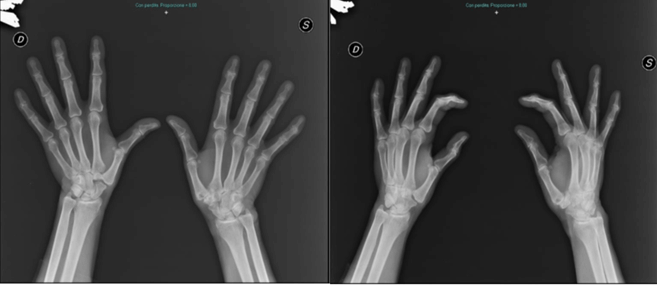

One year from the first surgical operation the patient asked to be treated on the increasingly sore left hand at the NPRS 9 (Numeric pain rating scale). Good positive results reported in literature regard arthroplasty with implants of dual mobility trapeziometacarpal prosthesis have encouraged us to apply the patient for this treatment. We opted the for the Touch® by KeriMedical (KeriMedical Switzerland). Post-operative, the hand was immobilized for two weeks with a plaster cast for better patient-supported management. After the removal of the immobilization the patient has immediately started exercise for autonomous functional re-education, showing lesser stiffness and pain than the first operation of the right hand. No early and medium-term complications were observed. Results of the Quick Dash score are shown in (Table 4) and X-Ray views and clinical presentation are shown in (Figures 4-8).

Figure 4: X-Ray Preoperatory of left hand that shows Stage III according to Eaton and Littre classification.

Figure 5: X-Ray post operatory of left hand.

Figure 6: X-Ray Follow-up 6 months of left hand.

Figure 7: X-Ray Follow-up 1 year of left hand.

Interview and clinical examination of the patient, satisfied for both procedures, has allowed us to highlight a meaningful difference of pinch strength between right and left thumb, both in tip, palmar and lateral pinch tests. In fact, the best results about pinch strength were recorded on the left side treated with arthroplasty with dual mobility prosthesis, despite the function and recruitment of adductor muscles are similar. Another important clinical evidence is moderate shortening of the right thumb, treated with trapeziectomy, resulting in different anatomical attitudes in mild hyperextension of the first metacarpophalangeal joint and different muscle compensation for opposition movement with fifth digit, as showed in the pictures. Analysing the recreational actions, being the patient a retired carpenter he delights during the week in chores. He points out difficulty using the hammer with his right hand, preferring the nondominant hand even for the daily use of a kitchen knife or to open a jar. The degree of subjective satisfaction was comparable between the right and left hand with no significant differences for pain, tingling and difficulty sleeping due to pain. Until the last follow up no complications common to arthroplasty with prosthesis such as synovitis, dislocation, secondary instability, loosening, infection and osteolysis were pointed out [9]. The results of our report document that in the medium-term follow-up (12 months) the difference is considered good for arthroplasty with dual mobility prosthesis and satisfactory for trapeziectomy. Results assessed at 2 years the dash score value is better than 1 year; however, this is not in the good group (Table 5).

Figure 8: Follow-up 1 year. Left Hand that underwent prosthesis replacement was marked.